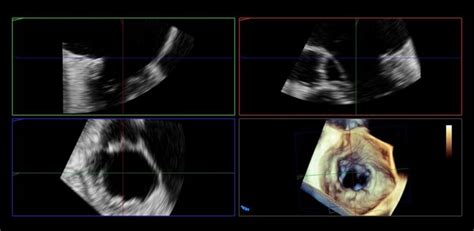

Existujú rôzne typy echokardiografie:

- Transtorakálna echokardiografia (TTE): Senzor sa umiestňuje na hrudnú stenu pacienta a cez ňu sa vizualizujú srdcové štruktúry a funkcie. Je neinvazívna a bezbolestná.

- Transezofageálna echokardiografia (TEE): Ultrazvuková sonda sa zavádza do pažeráka cez ústa alebo nos. Umožňuje detailnejšiu vizualizáciu srdcových štruktúr, najmä chlopní, aorty a srdcových prepážok, pričom sa vyhýba obmedzeniam spôsobeným kosťami hrudníka a pľúcami. Toto vyšetrenie je invazívnejšie a vyžaduje si špecifickú prípravu.